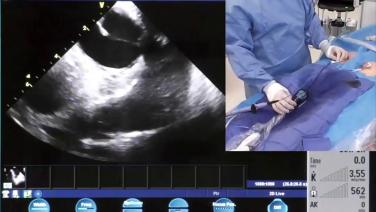

In the EP Lab - ICE & Mapping During the PVC Case with Andrew Brenyo, MD